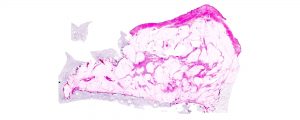

OBIO’s EAHN™ supports the evaluation of Huron Digital Pathology’s technology…

From https://eahn.obio.ca/new/obios-eahn-supports-the-evaluation-of-huron-digital-pathologys-technology-solutions-for-faster-and-more-accurate-diagnoses/: Sept 13, 2023 (Toronto, ON) – Hospitals generate thousands of pathology slides and reports each month. If harnessed, this…

Huron Digital Pathology partners with the University of Toronto and…

Huron Digital Pathology partners with the University of Toronto and Ontario Hospitals to build transformative, AI-powered tools for Province's pathology…